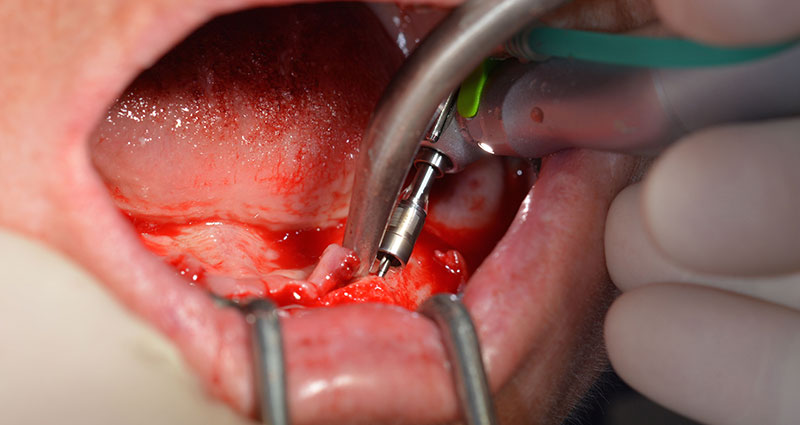

Nach der Entfernung der Unterkiefer-Restbezahnung erfolgte die krestale Schnittführung von Regio 37 bis Regio 47.

Zunächst wurde das Foramen mentale als limitierende anatomische Struktur dargestellt und die krestale Kortikalis mit dem geraden Handstück und einem großen Rosenbohrer geglättet (Abb. 4).